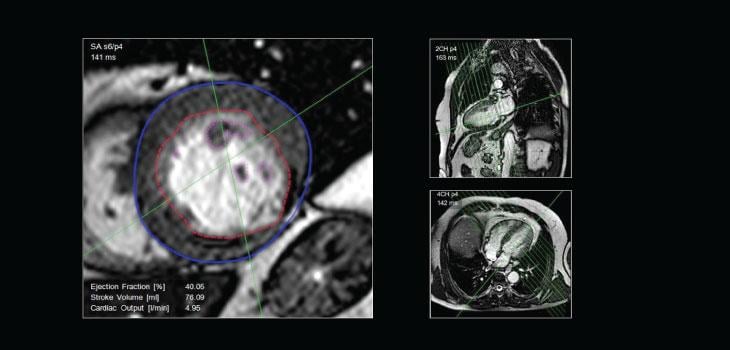

Among existing imaging modalities, cardiovascular magnetic resonance imaging (CMR) plays a role of growing importance in the assessment of patients with heart failure (HF). Currently, it is difficult to study the myocardial perfusion status in HF due to left ventricular (LV) remodeling and wall thinning, coexistent scars and respiratory artefacts. There is an urgent need for state-of-the-art imaging modalities with software algorithms to diagnose cardiovascular diseases accurately and at an early stage. In response to this need, PMI developed CAAS MRV, a sophisticated software that provides quantitative analyses of cardiovascular magnetic resonance images.

Left and right ventricular analysis from CMR datasets and blood flow measurements from velocity-encoded MR will assist the medical specialist in selecting the best treatment options. For flow analysis, PMI offers CAAS MR Flow and recently released its highly innovative CAAS MR 4D Flow to complete its CMR analysis portfolio.